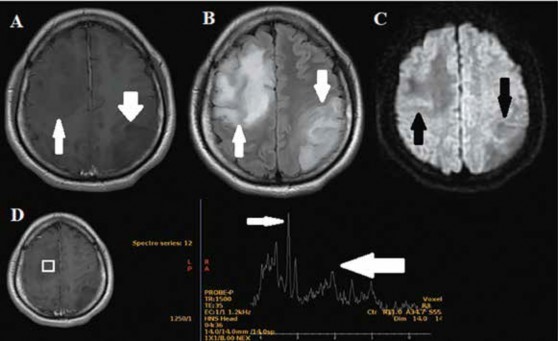

Se le realiza una resonancia magnética (RMN) cerebral contrastada en la que se evidencia, en imagen ponderada en T1, dos lesiones hipointensas no captadoras de contraste en región frontal derecha (que involucraba el borde anterior del área motora) y parietooccipital izquierda, ambas con edema vasogénico perilesional, que eran suprimidas en la secuencia de FLAIR; en el estudio de difusión restringen levemente y tienen un pico de colina en la espectroscopia, hallazgos compatibles con glioma de bajo grado (Figura 1).